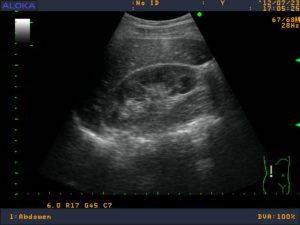

image

При проведении УЗИ оцениваются параметры почек:

1. размеры органа;

2. форма и контур;

3. подвижность;

4. однородность;

5. эхогенность паренхимы;

6. структуру чашечек и лоханок;

7. конкременты;

8. риск появления новообразований.

Обнаруживает УЗИ признаки хронического пиелонефрита:

1. об инфильтрации почечных тканей свидетельствует неровность контура;

2. за счет отека при одностороннем поражении наблюдается асимметрия размеров;

3. деформация чашечно-лоханочной зоны почки или ее расширение, а также состояние паренхимы (диффузная неоднородность) говорит об обструктивном (вторичном) характере заболевания, гидронефрозе или врожденной аномалии;

4. ограниченная дыхательная подвижность  свидетельствует об отеке паранефральной клетчатки;

5. при остром течении пиелонефрита может наблюдаться неоднородность плотности  тканей из-за очаговых воспалений,

6. при хроническом – повышенная эхогенность;

7. увеличение почки или снижение подвижности органа – признак острого течения пиелонефрита.